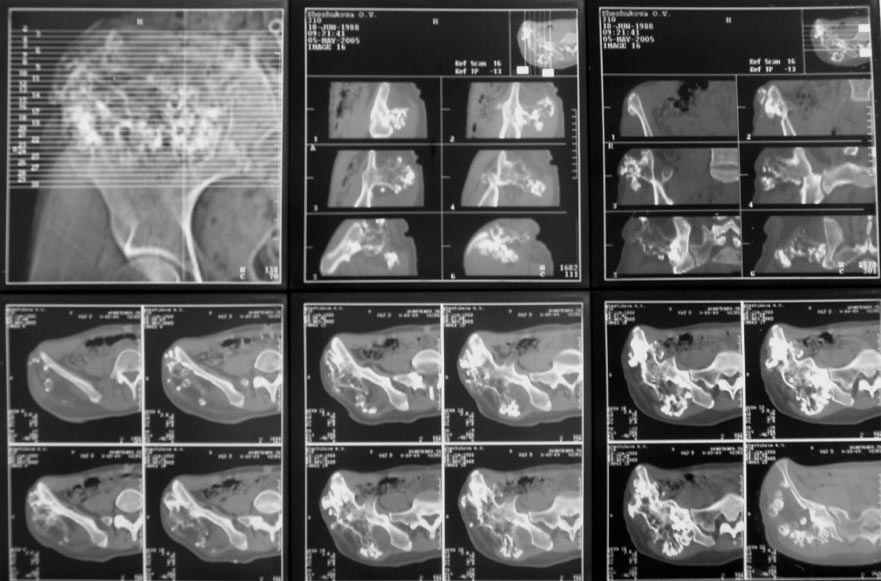

Судя по КТ, проблема не в гребне а в крыле...

Опухоль имеет задне-наружное нправление...

В таких ситуация 3D реконструкция по КТ - идеальная вещь...

По-моему, КТ-картина наводит на мысль об озлокачествлении (резкая неоднородность, местами размытие контуров) - вторичной хондросаркоме. Местами, кстати, имеется рост и в направлении брюшной полости. Для решения вопроса об объеме резекции в данном случае оправдана трепанобиопсия. Если это хондросаркома, особенно низкодифференцированная, то стоит обсудить возможность удаления всего крыла с окружающими мягкими тканями. Вариант реконструкции - комбинированная пластика аллотрансплантатами. А вот какими - зависит от наличия костного банка и возможностью индивидуального изготовления трансплантатов. При отсутствии таковой не лучше ли направить ее в ЦИТО?

В данный момент была выполнена биопсия новообразования. Материал в работе.